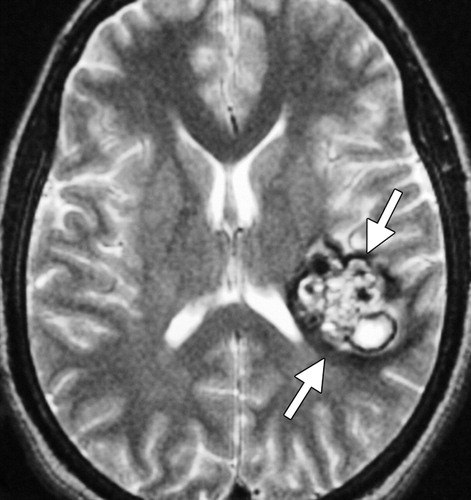

Т2 ви образование 108 фото